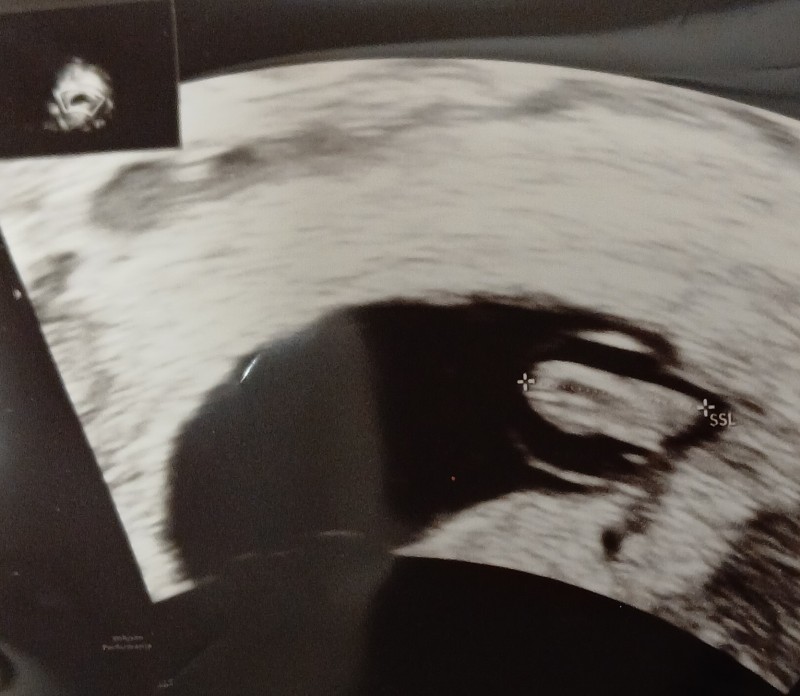

bebeğimiz kız mı erkek mi görebiliyor musunuz?

image

Erkek olabilir

Bana da kız gibi geldi

Bana kiz gibi geldi acikcasi

Sizinki de kız sanki

Erkek hissettim